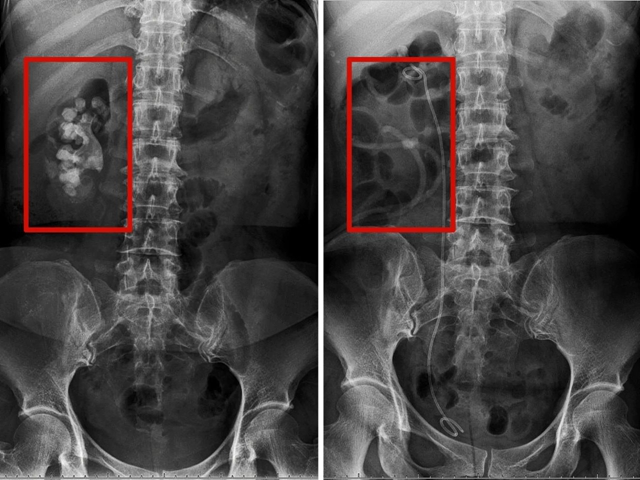

左:术前 右:术后

术后复查腹部平片显示结石几乎全部取出,汪先生十分满意。